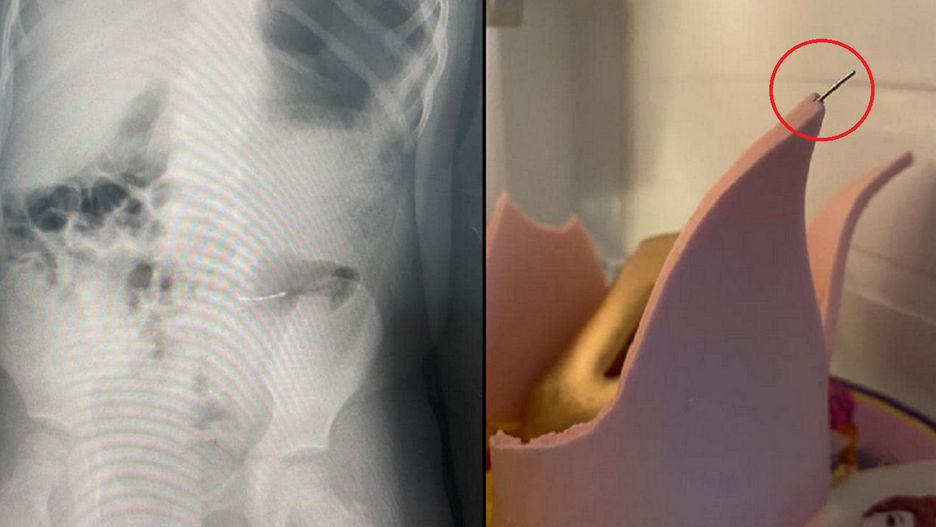

Dziewczynki zjadły tort, ale szybko zorientowały się, że połknęły przy tym coś twardego. Kiedy rodzina obejrzała ciasto zauważono, że ozdobna korona jest połączona metalowymi cienkimi szpilkami o tępym zakończeniu.

Rodzice natychmiast zabrali dziewczynki do szpitala. Po prześwietleniu okazało się, że obie połknęły metalowe elementy. Dostały lekarstwa, a lekarze czekają aż szpilki zostaną wydalone przez organizm w sposób naturalny.